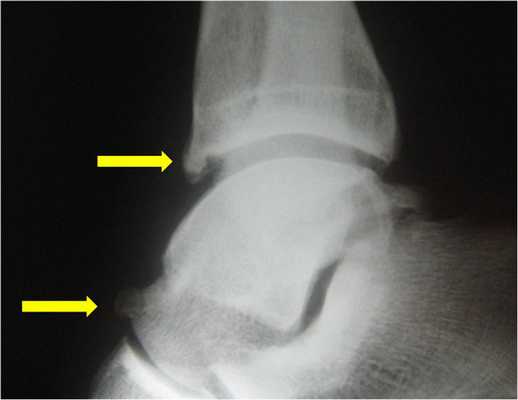

Рентгенография, КТ позволяют визуализировать краевые остеофиты и свободные внутрисуставные костные фрагменты.

Пациенту обязательно назначают рентгенограмму. На рентгенологическом снимке доктор легко увидит остеофиты - костные разрастания, появившиеся из-за воспалительного процесса. Дополнительно выполняется снимок в стрессовом положении. На нем доктор определит, есть ли соударение костей.

- Рентгенография плечевого сустава. Базовое исследование с достаточно низкой информативностью. Позволяет исключить некоторые патологии, установить размер субакромиального пространства, обнаружить остеофиты и участки кальцификации в мягких тканях.